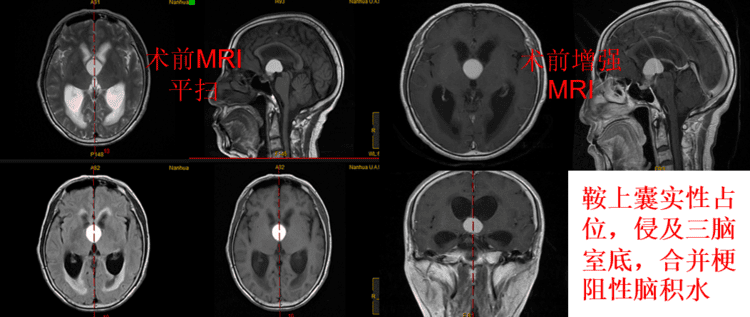

患者,陈某,67岁。因“反应迟钝、记忆力下降半年”入院。入院时MRI示鞍区占位并梗阻性脑积水,考虑为颅咽管瘤可能性大。

术后MRI增强可见肿瘤全切,脑积水解除